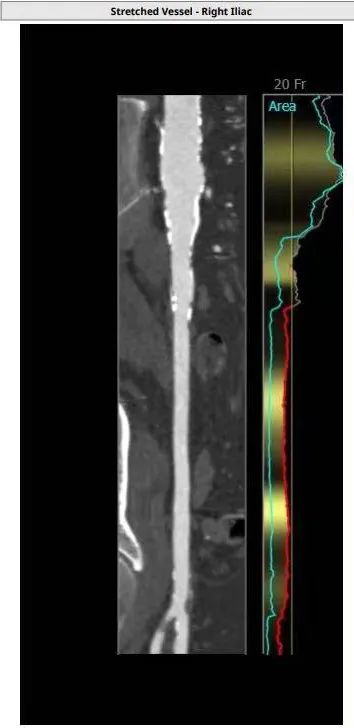

对于TAVR准备阶段,以国内现在大规模使用的自展瓣为例,通常需要使用20F的大鞘,CT分析入路情况是保证手术安全的前提,除常规需要5.5甚至是6.0以上的股动脉内径外,股动脉的钙化情况,proglider的熟练使用都是避免血管相关并发症的前提,当然,术中出现入路并发症,也需丰富的经验来判断风险,手术是否能继续,术前需要准备什么耗材都是处理入路并发症的前提,广东省人民医院TAVR团队术前除常规耗材外,还常备外周8*60高压球囊及外周支架以备不时之需。